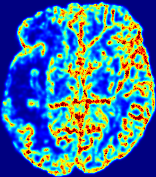

LesionRefer to captionRefer to captionRefer to captionRefer to captionRefer to captionRefer to caption𝐕rgbsubscript𝐕𝑟𝑔𝑏{\bf{V}}_{rgb}Refer to captionRefer to captionRefer to captionRefer to captionRefer to captionRefer to caption𝐕2subscriptnorm𝐕2{\|\bf{V}}\|_{2}Refer to captionRefer to captionRefer to captionRefer to captionRefer to captionRefer to captionRefer to caption3.53.53.52.82.82.82.12.12.11.41.41.40.70.70.70.00.00.0(mm/s)𝑚𝑚𝑠(mm/s)D𝐷DRefer to captionRefer to captionRefer to captionRefer to captionRefer to captionRefer to captionRefer to caption0.0200.0200.0200.0160.0160.0160.0120.0120.0120.0080.0080.0080.0040.0040.0040.0000.0000.000(mm2/s)𝑚superscript𝑚2𝑠(mm^{2}/s)Slice #1Slice #2Slice #3Slice #4Slice #5Slice #6

Figure 4: PIANO feature maps for another patient in the ISLES 2017 training set, where the lesion is located in the right hemisphere. Top row: segmented stroke lesion region (white) on different slices. The corresponding slices for the PIANO feature maps are shown in the following rows.

For a better insight into an estimated velocity field 𝐕𝐕{\bf{V}} and diffusion field 𝐃𝐃{\bf{D}}, we compute the following maps: (1) 𝐕rgbsubscript𝐕𝑟𝑔𝑏{\bf{V}}_{rgb}: Color-coded orientation map of 𝐕=(Vx,Vy,Vz)T𝐕superscriptsuperscript𝑉𝑥superscript𝑉𝑦superscript𝑉𝑧𝑇{\bf{V}}=(V^{x},V^{y},V^{z})^{T}, obtained by normalizing 𝐕𝐕{\bf{V}} to unit length and mapping its 3 components to red, green, blue respectively; (2) 𝐕2subscriptnorm𝐕2\|{\bf{V}}\|_{2}: 222 norm of 𝐕𝐕{\bf{V}}; (3) D𝐷D: scalar field in Eq. 5.

Fig. 3 and Fig. 4 show the PIANO feature maps estimated from two ISLES 2017 patients: all are highly consistent with the lesion in both cases. Details of the blood flow trajectories are revealed in 𝐕rgbsubscript𝐕𝑟𝑔𝑏{\bf{V}}_{rgb} by the ridged patterns and the sharp changes of colors in the unaffected (right) hemisphere, while the flat patterns appearing within the lesion provide little directional information about the velocity and indicate low velocity magnitudes. Velocity magnitudes are more directly visualized via 𝐕2subscriptnorm𝐕2\|{\bf{V}}\|_{2}, from which one can easily locate the lesion where 𝐕2subscriptnorm𝐕2\|{\bf{V}}\|_{2} is low. D𝐷D also indicates lower diffusion values in the lesion, though with less contrast potentially due to the fact that it captures the accumulated effect of CA diffusion at the voxel-level.